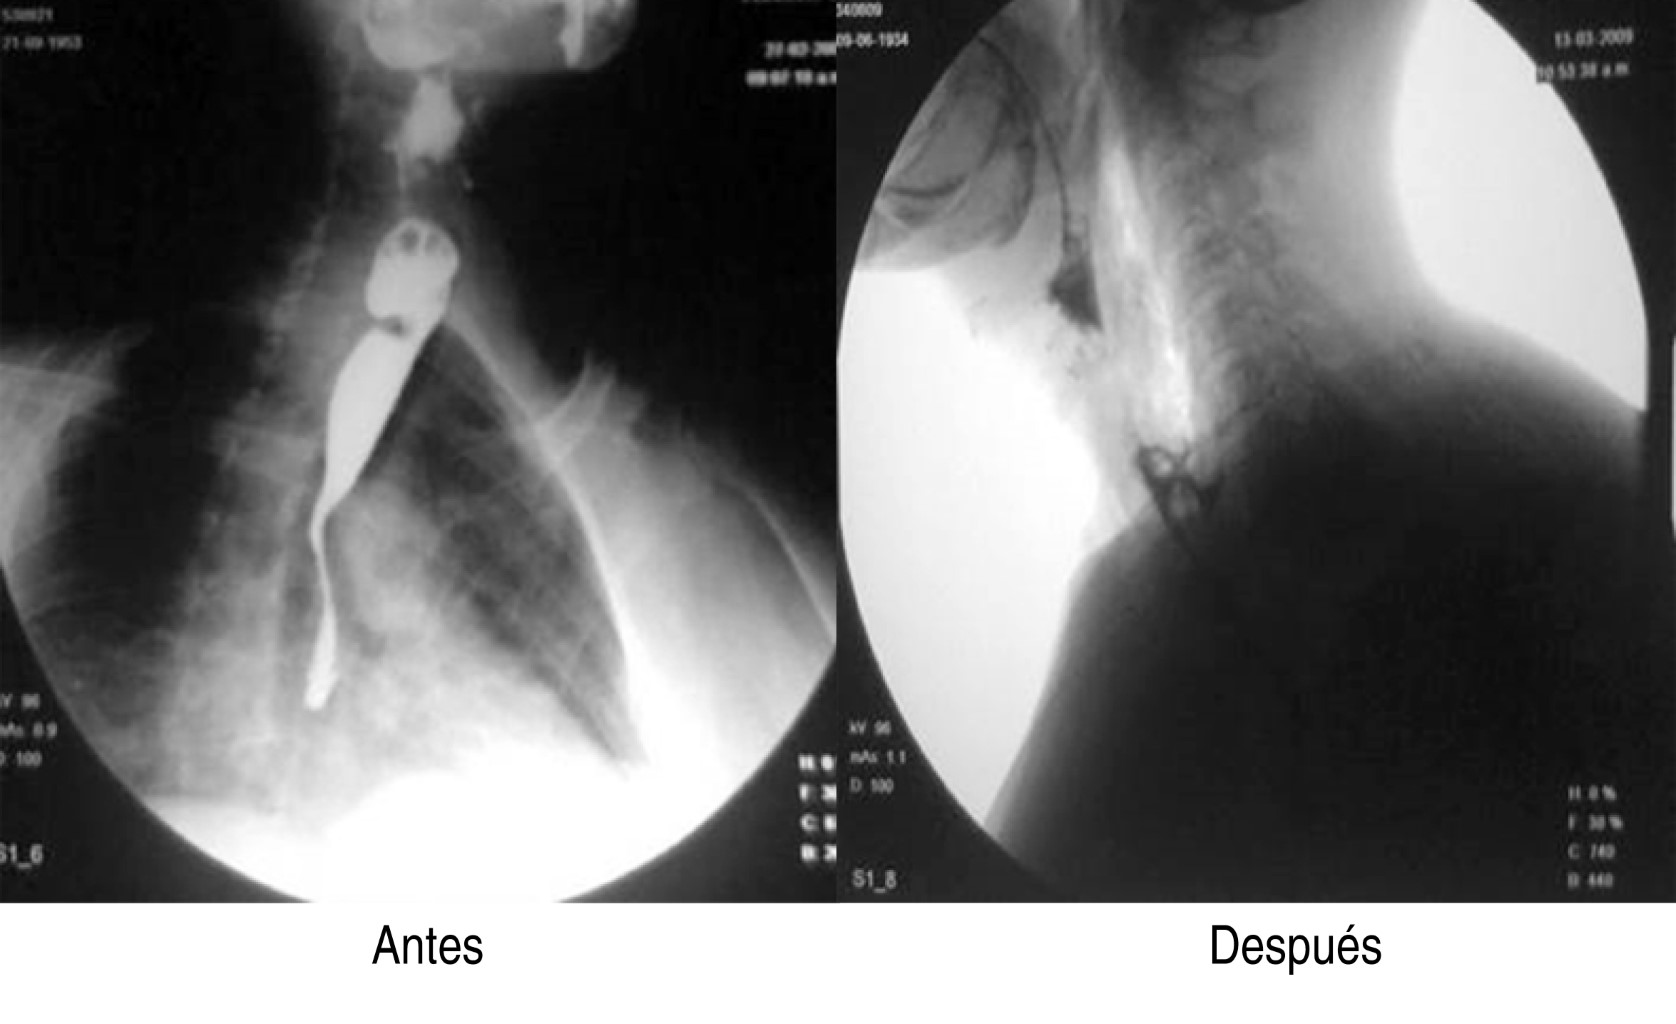

A todos los pacientes se les tomaron datos clínicos demográficos, tales como: edad, sexo, tiempo de evolución de los síntomas y síntomas predominantes, características del divertículo, remisión de los síntomas y necesidad de reintervención. El diagnóstico de divertículo de Zenker se realizó por medio de estudio radiológico de contraste (esofagograma con medio de contraste baritado) y endoscópico, con lo cual se confirmaba el diagnóstico y se calculaba el tamaño del divertículo (Figura 1).

Se realizaron en total 18 procedimientos, se consideró como complicación sólo un paciente (7.1%), quien presentó sangrado importante, mismo que se controló, pero impidió en el procedimiento inicial completar adecuadamente la miotomía, por lo que se reintervino a las 24 horas para completar ésta. Durante los procedimientos, dos pacientes tuvieron enfisema subcutáneo (un paciente femenino de 74 años y uno masculino de 57 años), los cuales fueron tratados de forma conservadora mediante la administración de una cefalosporina de tercera generación, así como control radiográfico para medición del enfisema subcutáneo (Figura 6). No se presentaron complicaciones mayores como mediastinitis, hemorragia incoercible o perforación que requirieran cambiar el tratamiento endoscópico por el quirúrgico de urgencia o programado. La mejoría de la disfagia en todos los casos fue inmediata y en las consultas subsecuentes refirieron haber aumentado de peso, además se realizó endoscopia y trago de material de control (Figura 7).

Figura 1

Figura 7